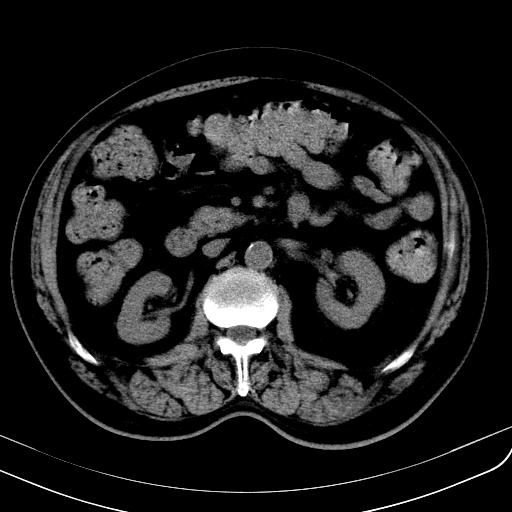

胃底靠近胃大弯处可见一圆形软组织影,直径为3.45cm,ct值约为30.1hu